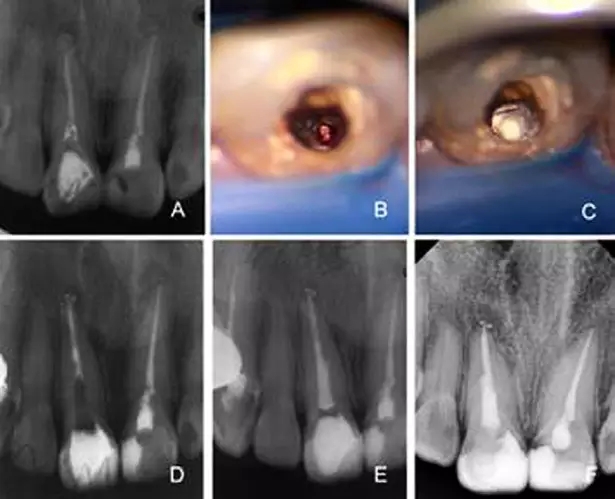

A:根管唇側(cè)穿孔,牙膠尖于穿孔處超填,根尖及近中側(cè)方有骨密度減低

影像 B:根管顯微鏡輔助下取出牙膠尖 C:MTA修補側(cè)穿孔 D:根管部分

充填 E:2月后根管及冠方充填 F:8個月后復(fù)查X線片可見暗影區(qū)減小

而在手術(shù)顯微鏡下術(shù)者可以對根管壁穿孔的位置、大小及形態(tài)等多個方面進行仔細的定位和評價。對于根管穿孔的病例,新鮮的穿孔要即刻修補,陳舊的穿孔用超聲器械對局部進行清潔和預(yù)備,Ca(OH)2封藥一周后再進行修補。治療中在建立直線通路后,顯微鏡下先用輸送器準(zhǔn)確放置修補材料,加壓壓實后充填,拍攝x線片,確認形成良好的根尖屏障,再對剩余根管進行常規(guī)充填,這方法可明顯提高根管壁穿孔非手術(shù)治療的成功率[10]。M TA是近年來逐漸被廣泛用于根管穿孔修補及根尖封閉的材料。M TA具有良好的封閉性、生物相容性,不溶于血液及組織液,并且具有x線阻射性,是一種較理想的根尖倒充填材料。顯微鏡下使用MTA修補根管壁穿孔,患牙治療成功率可達86%[11、12]。